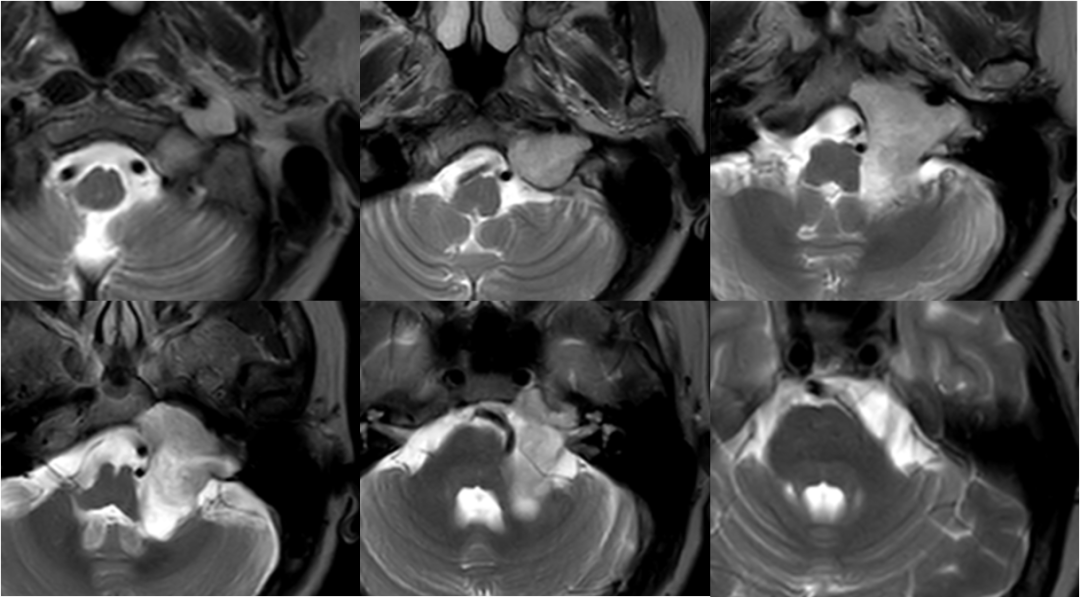

术后影像

![]()